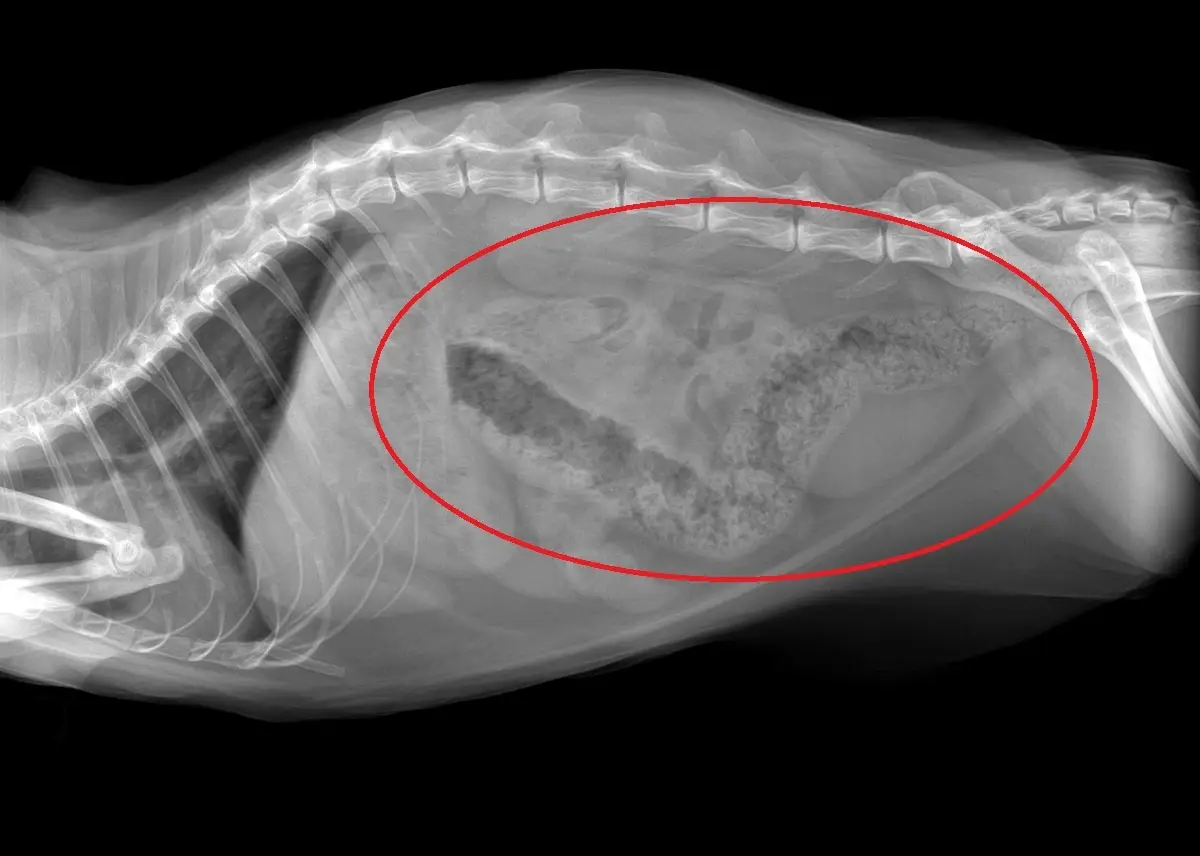

- X -hays أو الموجات فوق الصوتية للنظر في الجهاز الهضمي للأورام أو الاورام الحميدة.

- تنظير القولون: هذا الإجراء ينطوي على إدخال أنبوب رفيع مع كاميرا في النهاية لتقييم القولون للحصول على علامات النزيف الداخلي والالتهاب والروحال والسرطان. يمكن أخذ الخزعات الآن للتقييم المجهري.